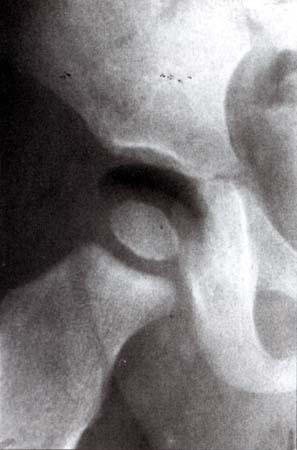

«Вакуум-эффект» применяется в педиатрии у начавших хромать детей для установления наличия выпота в полости тазобедренного сустава. Методика проста: с помощью специального устройства производится тракция нижней (больной, естественно) конечности до наступления характерного щелчка, после чего производится рентгенография. При наличии избыточного количества жидкости суставная щель расширяется, но газа в суставе не наблюдается. В норме же имеет место описанный выше эффект с образованием в полости сустава свободного газа.

Больной мужчина 48 лет поступил в отделение нейрохирургии с болями в поясничном отделе позвоночника, корешковыми жалобами. Оперирован 4 года назад по поводу грыжи диска L4-5 (гемиламинэктомия L4). На обзорных снимках поясничного отдела позвоночника выявлены признаки остеохондроза, смещение тел L3, L4 кзади на 3 и 4 мм соответственно. Для исключения гипермобильности были произведены функциональные рентгенограммы в положении максимального сгибания и разгибания, на которых значительного увеличения листеза выявлено не было, отмечалось увеличение вертикальной подвижности тел позвонков (в основном в сегментах L3-4и L4-5).

Кроме того, в проекции дисков L3-4, L4-5 и L5-S1 визуализировались треугольной формы просветления газовой плотности, которые и были расценены как «вакуум-феномен» (на данной рентгенограмме газ чётко виден только в диске L3-4)

Данное наблюдение представлено всего одним случаем и имеет целью ознакомить коллег с ним воочию, так как этот эффект в практике рентгенолога встречается довольно редко.

Название случая - "Любителям Вакуум-феномена".

Женщина, 50 лет. Обследовалась по поводу шейного остеохондроза, вертебро-базиллярной недостаточности.

Да - это "вакуум-феномен". Вот как раз плечевой сустав - это не столь частая локализация, в отличие от коленных суставов и дисков.